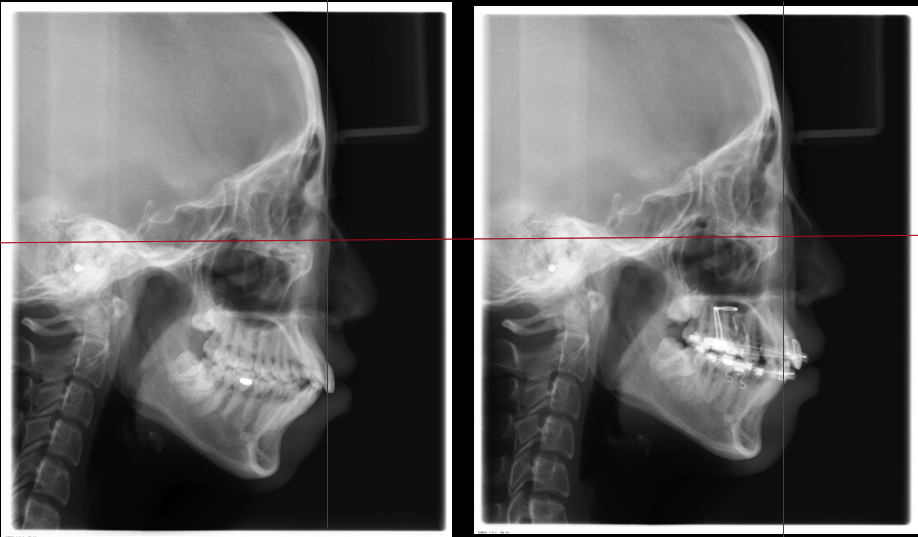

_PRE-TXNorm FMIA°47°55.0SNA°77.7°83.0SNB°70.2°80.0ANB°7.5°3.0FMA° 29.826PFH/AFH70.5°70Z Angle°50.3°77U1-FH113.0110.0IMPA°103.297.0U Lip to s’ line6.3 mm5.0L Lip to s’ line3.9 mm3.0OP-FH1215

头侧位片:

▲下颌后缩,骨性Ⅱ类

▲高角,颏部发育不足

▲上下前牙唇倾

Post-TXPRE-TXPost-TXNormFMIA°47°57.555.0SNA°77.7°76.883.0SNB°70.2°73.780.0ANB°7.5°3.13.0FMA° 29.828.026PFH/AFH70.5°65.970Z Angle°50.3°64.477U1-FH113.0103.7110.0 IMPA°103.291.197.0U Lip tos’ line6.3 mm3.25.0L Lip to s’ line3.9 mm1.03.0OP-FH1212.615